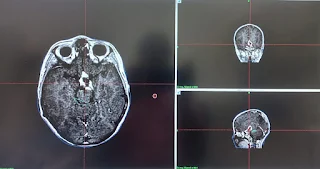

Follow up MRI brain with contrast dated December 29, 2022 shows significant regression in tumor volume from 41 cc to 5.7 cc.

Patient visited the gamma knife center for first routine Follow up presented with good health and no symptoms.Follow up MRI brain with contrast dated July 06, 2023 shows significant regression in tumor volume as reported previously.